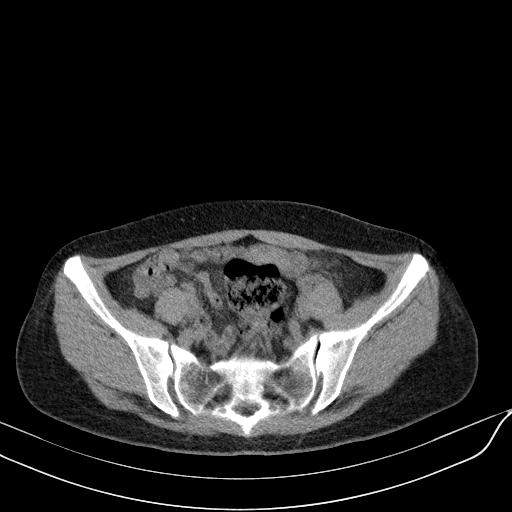

标题: CT23965:无外伤史,下腹痛 [打印本页]

标题: CT23965:无外伤史,下腹痛

肠道未准备,继续往下扫,乙状结肠占位不排除。建议钡灌或结肠镜检查。

乙状结肠占位不排除

未见明显异常改变,做个气钡双重造影除外一下结肠病变,无外伤史为啥不常规喝泛影葡胺水对比剂再扫ct呢?

扫描时应做肠道准备,口服稀释造影剂。

回肠间质瘤?

肠道肿瘤,建议行钡剂灌肠检查。